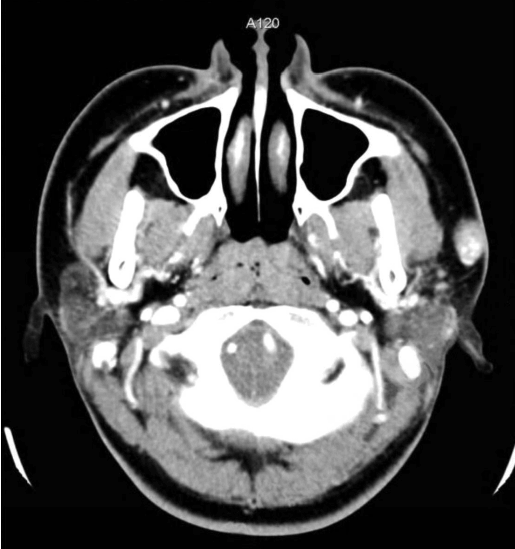

문 2. 표피 바로 아래 발생한 종괴가 있는 24세 여자 환자의 경부 컴퓨터단층촬영이다. 진단은?

① Epidermal cyst

② Pleomorphic adenoma

③ Pilomatrixoma

④ Warthin’s tumor

⑤ Squamous cell carcinoma

문 2. 답

해설 Pilomatrixoma는 피부에 붙어 있는 형태로 내부에 석회화가 관찰된다.